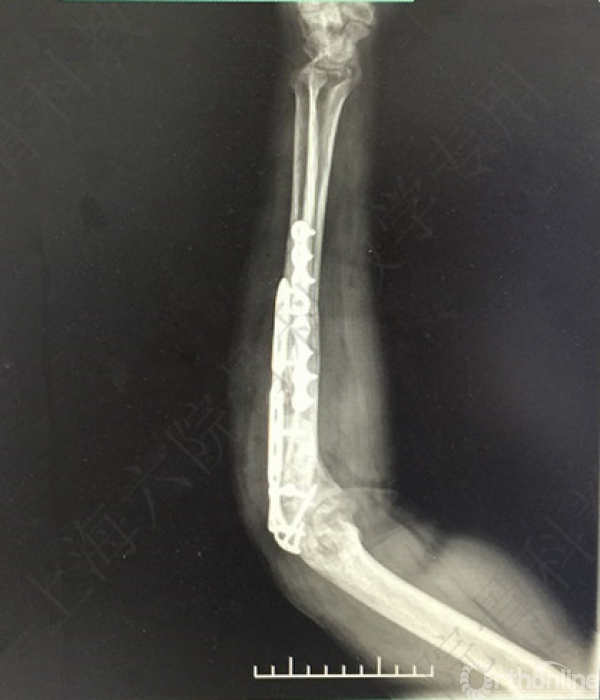

术后X线片示:左尺桡骨骨不连术后,对位对线可,内固定牢靠,桡骨头切除,肘关节在位。

医方第一次术后,未能纠正骨折力线,未发现桡骨头脱位,手术方式和操作欠妥当。存在对疾病评估不足,漏诊,手术方式不当,手术操作不当,术后并发症观察及处理不当等过失。